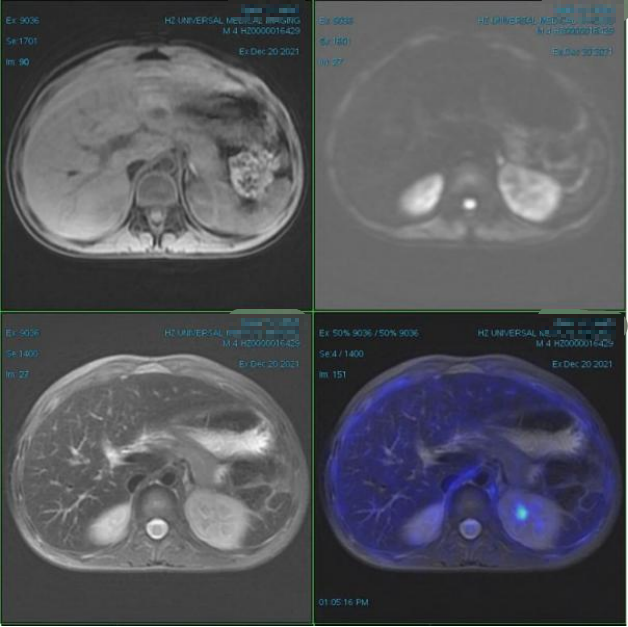

放疗后复查:2021.12.21PET/MR:术区未见明确肿块,FDG代谢未见明显异常;全身多处骨骼局部骨质信号异常,FDG代谢未见异常增高,考虑骨转移治疗后改变。

疗效评估:CR。